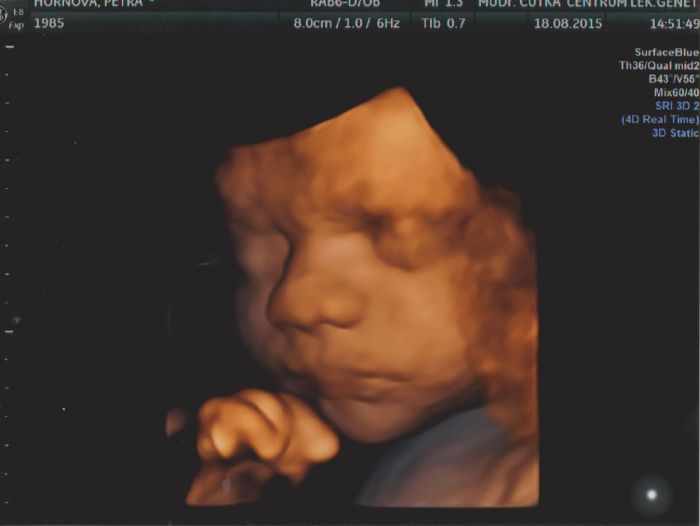

Autor: Peťa_85 18.8.2015 v 16:04

Ahoj maminky :)

tak jsme se vrátili z 4D ultrazvuku a musím říct, že to byl vážně nádherný zážitek. Stálo nás to teda 1000,- ale zase máme černobílé i barevné fotky a cca 15 minut videa. Malý sice dělal chviličku obstrukce a zakrýval si obličejíček ručkou, ale nakonec se teda ukázal a šklebil se na nás a zíval. Posílám i jednu barevnou fotku. Kdo nebyl a uvažuje o tom, tak určitě doporučuji.